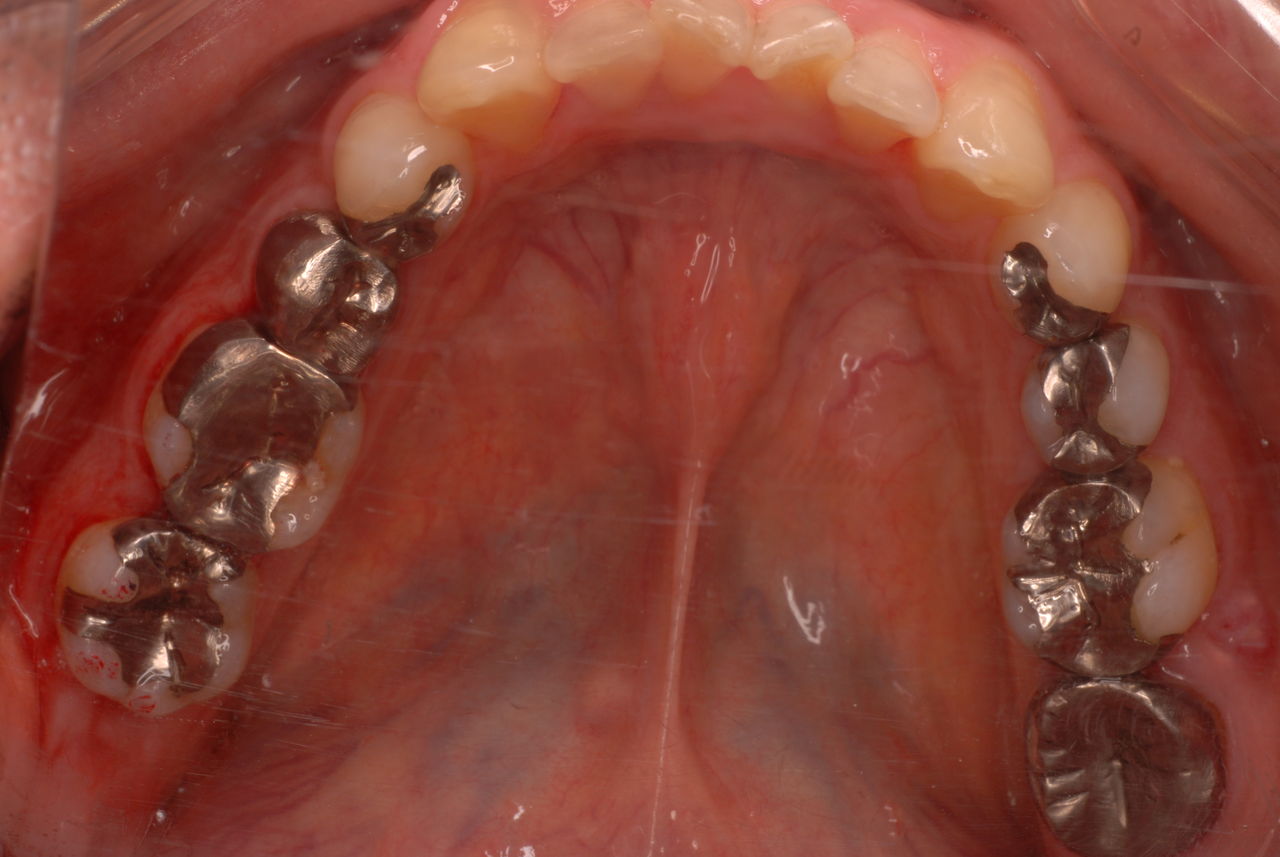

なかなかブラシの使い方ができていないようで、歯磨きと歯周病でのブラシの使い方は別なのですが、習ったことも検査もされずに金属を被せたりしているようで、これからも歯医者さんで抜かれたり、その後にインプラントのような高価な“クギ”を打ち込まれる方が増えるかと思うと残念です。

被せても、詰めても病気は治らないのですから。又病気の元になり易い不適合な差し歯や金属、インプラントがあればそこからバイキンが侵入して体に悪さもしやすいのではないかと心配しています。